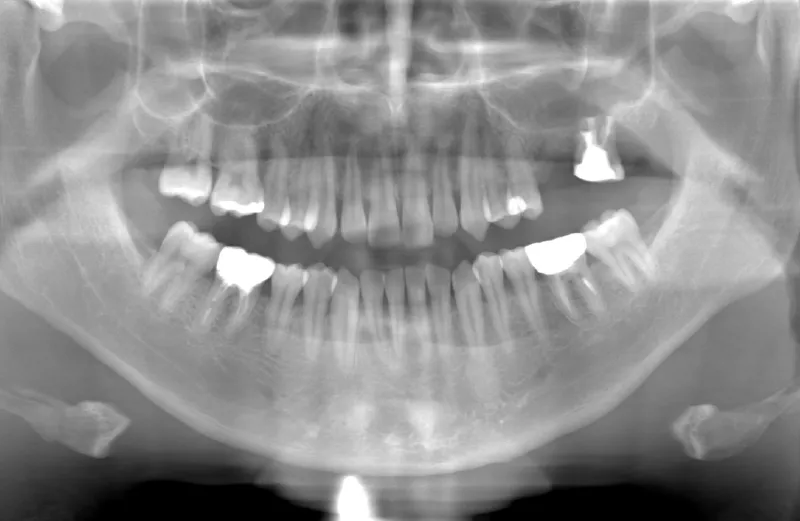

メガジェンオペ症例

メガジェンオペの症例紹介01

治療前

治療後

| 主訴 | 上入れ歯は以前に入れたことがあるが違和感が強く入れられなかったのでインプラントで治療して欲しい。 他院では上顎洞までの垂直骨量が1~3mm程度しかないのでサイナスリフトが必須であり、インプラント治療で歯が入るまでに1年以上かかると言われたのでセカンドオピニオンを希望で来院。 |

|---|---|

| 治療期間 | 2.5ヶ月で仮歯が入り、 4ヶ月で最終補綴物が入って終了。 |

| 費用 | 約1,500,000円 |

| 治療内容 | エクストラワイドショートインプラントを埋入し、上顎洞を移植材を用いずに挙上しインプラントを埋入した。約2.5ヶ月で仮歯を装着し、様々な機能面に問題がないことを確認し4ヶ月で最終補綴物を装着して終了した。 |

| 治療のリスク | インプラント埋入オペ時に術者が上顎洞内にインプラントを迷入させる可能性がある。これは術者が技術的に熟練していれば防ぐことが可能。 |